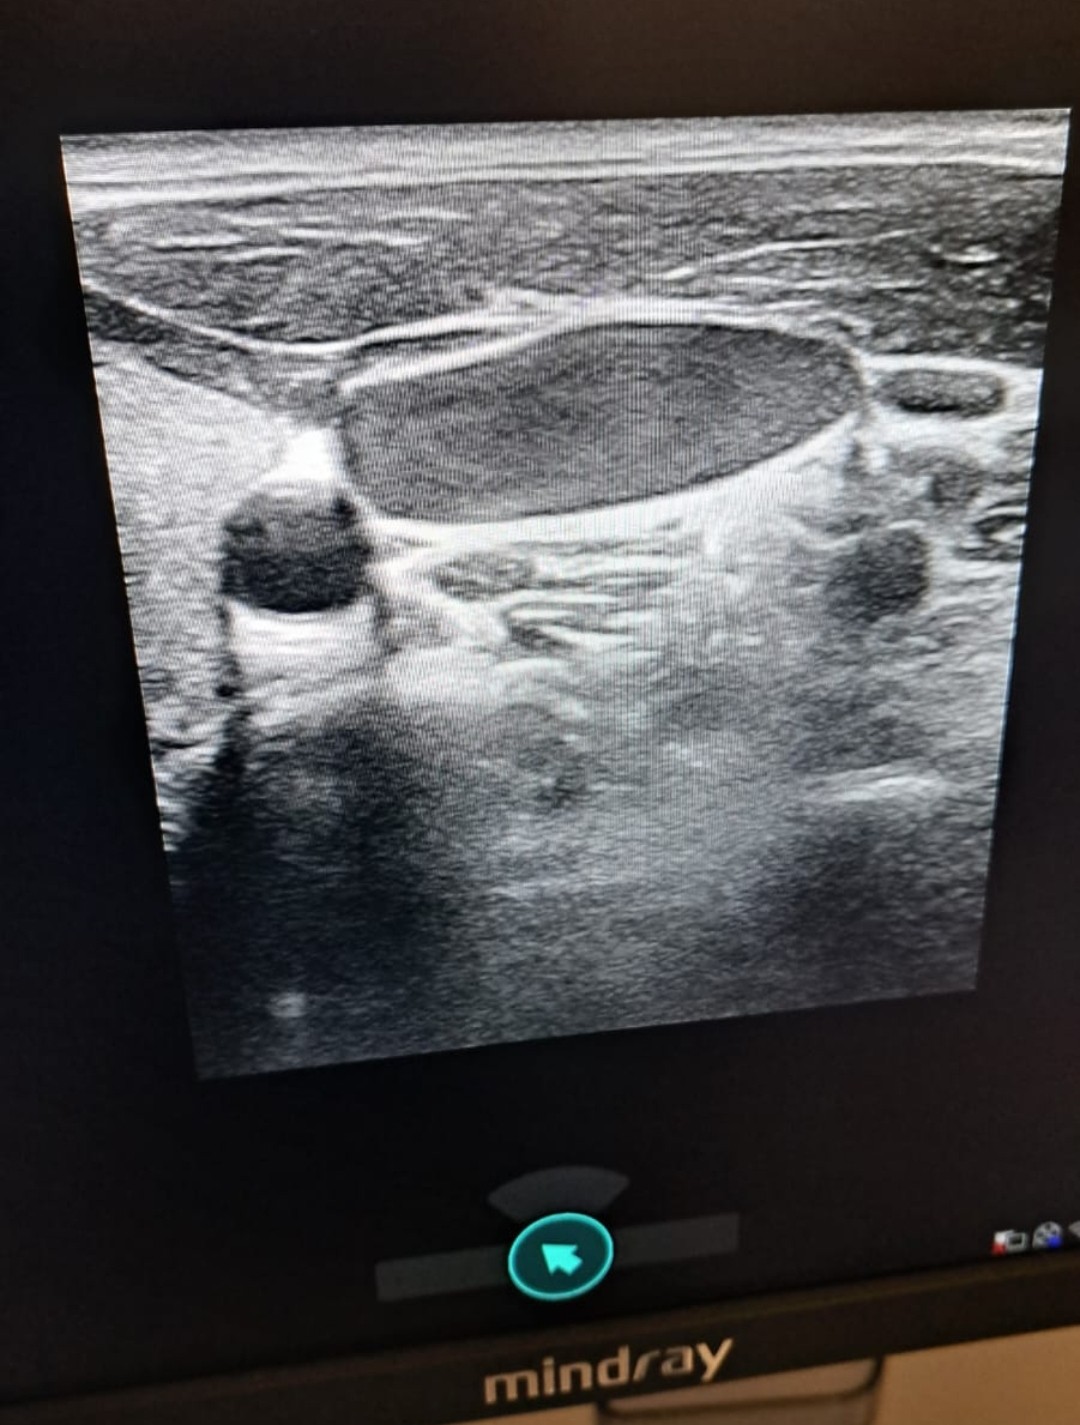

Hallazgos ecográficos

Se decide ante esta exploración física ecografía en el centro de salud en ese momento: tiroides normal, no adenopatías de características sospechosas de malignidad; se observa vena yugular izquierda con flujo aplanado monofásico, con aumento del tamaño de esta y que comprime perfectamente.

JC: Disfagia con vena yugular ingurgitada que indica posible obstrucción en nivel inferior. Se realiza consulta a cirugía vascular con la imagen estática y videos de la ecografía, quienes nos indican que es normal que al comprimir desaparezca la señal Doppler.